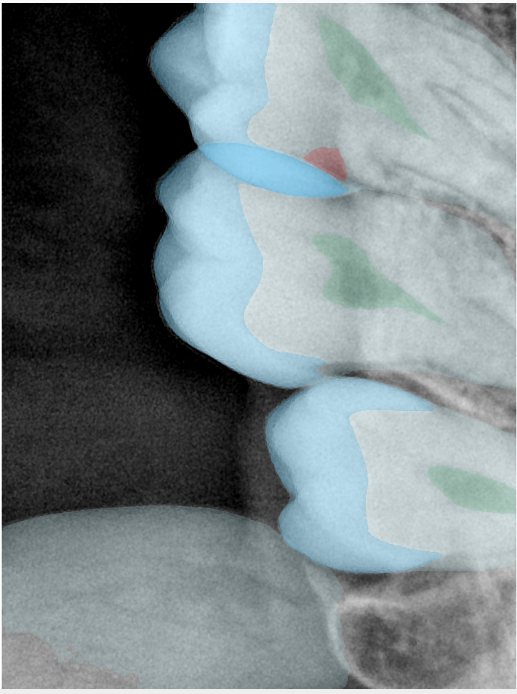

第三版算法分辨率效果比较

Updated: 2026-04-13(更新日期)

| 编号 | 原图 | 第一版 | 第二版 | 第三版 1216x1600 | 第三版 768x1024 | 第三版 1120x1120 |

|---|---|---|---|---|---|---|

| 131315.jpg | ![]() | ![]() | ![]() | ![]() | ![]() | ![]() |

| 131316.jpg | ![]() | ![]() | ![]() | ![]() | ![]() | ![]() |

| 131317.jpg | ![]() | ![]() | ![]() | ![]() | ![]() | ![]() |

| 131318.jpg | ![]() | ![]() | ![]() | ![]() | ![]() | ![]() |

| 131319.jpg | ![]() | ![]() | ![]() | ![]() | ![]() | ![]() |

| 131320.jpg | ![]() | ![]() | ![]() | ![]() | ![]() | ![]() |

| 131321.jpg | ![]() | ![]() | ![]() | ![]() | ![]() | ![]() |

| 131326.jpg | ![]() | ![]() | ![]() | ![]() | ![]() | ![]() |

| 131327.jpg | ![]() | ![]() | ![]() | ![]() | ![]() | ![]() |

| 131328.jpg | ![]() | ![]() | ![]() | ![]() | ![]() | ![]() |

| 131330.jpg | ![]() | ![]() | ![]() | ![]() | ![]() | ![]() |

| 131331.jpg | ![]() | ![]() | ![]() | ![]() | ![]() | ![]() |

| 131332.jpg | ![]() | ![]() | ![]() | ![]() | ![]() | ![]() |

| 131333.jpg | ![]() | ![]() | ![]() | ![]() | ![]() | ![]() |

| 131334.jpg | ![]() | ![]() | ![]() | ![]() | ![]() | ![]() |

| 131336.jpg | ![]() | ![]() | ![]() | ![]() | ![]() | ![]() |

| 131337.jpg | ![]() | ![]() | ![]() | ![]() | ![]() | ![]() |

| 131338.jpg | ![]() | ![]() | ![]() | ![]() | ![]() | ![]() |

| 131339.jpg | ![]() | ![]() | ![]() | ![]() | ![]() | ![]() |

| 131340.jpg | ![]() | ![]() | ![]() | ![]() | ![]() | ![]() |

| 131341.jpg | ![]() | ![]() | ![]() | ![]() | ![]() | ![]() |

| 131342.jpg | ![]() | ![]() | ![]() | ![]() | ![]() | ![]() |

| 131344.jpg | ![]() | ![]() | ![]() | ![]() | ![]() | ![]() |

| 131345.jpg | ![]() | ![]() | ![]() | ![]() | ![]() | ![]() |

| 131346.jpg | ![]() | ![]() | ![]() | ![]() | ![]() | ![]() |

| 131347.jpg | ![]() | ![]() | ![]() | ![]() | ![]() | ![]() |

| 131348.jpg | ![]() | ![]() | ![]() | ![]() | ![]() | ![]() |

| 131349.jpg | ![]() | ![]() | ![]() | ![]() | ![]() | ![]() |

| 131350.jpg | ![]() | ![]() | ![]() | ![]() | ![]() | ![]() |

| 131354.jpg | ![]() | ![]() | ![]() | ![]() | ![]() | ![]() |

| 131355.jpg | ![]() | ![]() | ![]() | ![]() | ![]() | ![]() |

| 131356.jpg | ![]() | ![]() | ![]() | ![]() | ![]() | ![]() |

| 131357.jpg | ![]() | ![]() | ![]() | ![]() | ![]() | ![]() |

| 131360.jpg | ![]() | ![]() | ![]() | ![]() | ![]() | ![]() |

| 131362.jpg | ![]() | ![]() | ![]() | ![]() | ![]() | ![]() |

| 131363.jpg | ![]() | ![]() | ![]() | ![]() | ![]() | ![]() |

| 131364.jpg | ![]() | ![]() | ![]() | ![]() | ![]() | ![]() |

| 131365.jpg | ![]() | ![]() | ![]() | ![]() | ![]() | ![]() |